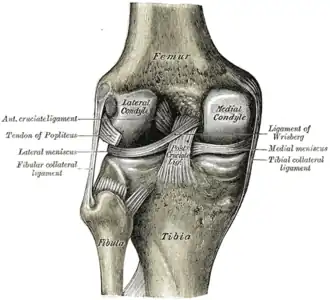

Ligaments

The ligaments surrounding the knee joint offer stability by limiting movements and, together with the menisci and several bursae, protect the articular capsule.[19]

Intracapsular

The knee is stabilized by a pair of cruciate ligaments. These ligaments are both extrasynovial, intracapsular ligaments.[20] The anterior cruciate ligament (ACL) stretches from the lateral condyle of femur to the anterior intercondylar area.[13] The ACL prevents the tibia from being pushed too far anterior relative to the femur.[13] It is often torn during twisting or bending of the knee.[21] The posterior cruciate ligament (PCL) stretches from medial condyle of femur to the posterior intercondylar area. This ligament prevents posterior displacement of the tibia relative to the femur.[13] Injury to this ligament is uncommon but can occur as a direct result of forced trauma to the ligament.

The transverse ligament stretches from the lateral meniscus to the medial meniscus. It passes in front of the menisci. It is divided into several strips in 10% of cases.[10]: 208 The two menisci are attached to each other anteriorly by the ligament.[22] The posterior (of Wrisberg) and anterior meniscofemoral ligaments (of Humphrey) stretch from the posterior horn of the lateral meniscus to the medial femoral condyle. They pass anterior and posterior to the posterior cruciate ligament respectively.[13][10]: 208 The meniscotibial ligaments (or "coronary") stretches from inferior edges of the menisci to the periphery of the tibial plateaus.

Extracapsular

The patellar ligament connects the patella to the tuberosity of the tibia. It is also occasionally called the patellar tendon because there is no definite separation between the quadriceps tendon (which surrounds the patella) and the area connecting the patella to the tibia.[23] This very strong ligament helps give the patella its mechanical leverage[24] and also functions as a cap for the condyles of the femur. Laterally and medially to the patellar ligament, the lateral and medial retinacula connect fibers from the vasti lateralis and medialis muscles to the tibia. Some fibers from the iliotibial tract radiate into the lateral retinaculum and the medial retinaculum receives some transverse fibers arising on the medial femoral epicondyle.[10]: 206

The medial collateral ligament (MCL a.k.a. "tibial") stretches from the medial epicondyle of the femur to the medial tibial condyle. It is composed of three groups of fibers, one stretching between the two bones, and two fused with the medial meniscus. The MCL is partly covered by the pes anserinus and the tendon of the semimembranosus passes under it.[10]: 206 It protects the medial side of the knee from being bent open by a stress applied to the lateral side of the knee (a valgus force).[10]: 206

The lateral collateral ligament (LCL a.k.a. "fibular") stretches from the lateral epicondyle of the femur to the head of fibula. It is separate from both the joint capsule and the lateral meniscus.[10]: 206 It protects the lateral side from an inside bending force (a varus force). The anterolateral ligament (ALL) is situated in front of the LCL.